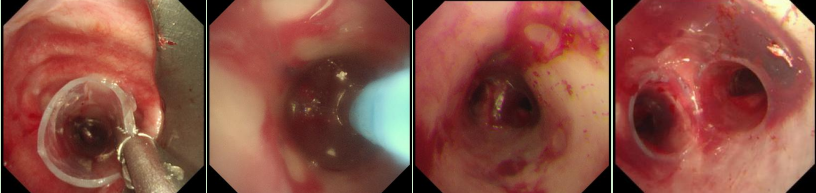

在硬質(zhì)支氣管鏡引導下,手術(shù)團隊首先對狹窄部位進行球囊擴張。隨后,將術(shù)前根據(jù)患者三維CT數(shù)據(jù)定制的Y型硅酮支架精準覆蓋于氣管狹窄段。該支架確保與患者自身的氣道解剖結(jié)構(gòu)完美貼合,實現(xiàn)最佳支撐效果,并最大限度減少粘膜刺激增生等特點。支架展開后穩(wěn)定支撐于隆突及雙側(cè)主支氣管,氣道狹窄立即得到解除。

隨著手術(shù)順利完成,趙先生蘇醒后自覺呼吸順暢,術(shù)后復查顯示支架位置良好,氣道通暢,呼吸困難癥狀顯著緩解。

王振靜說,硬質(zhì)支氣管鏡不僅為大氣道介入治療提供了穩(wěn)定的操作平臺,同時硅酮支架還具有可取出、可調(diào)整、不易刺激黏膜增生等特點,尤其對于良性氣道狹窄(如結(jié)核所致)的患者,既能解決當前通氣障礙,也為后續(xù)的治療提供了機會,改善了生活質(zhì)量。